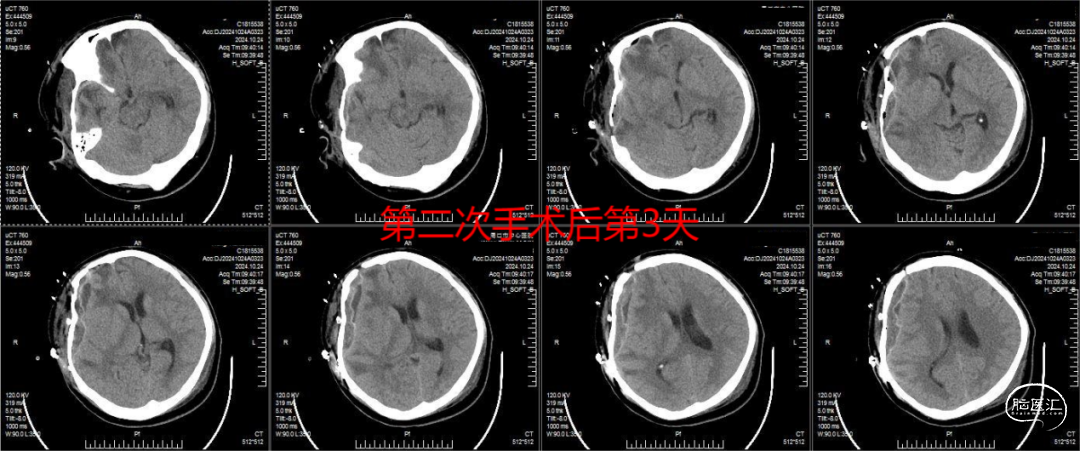

本例患者因车祸外伤行手术治疗,术中去除颅骨约12cm×10cm,行颅骨修补剥离颞肌期间出现硬脑膜破损,虽术中行自体肌肉修补,但二次手术探查中发现仍存在脑脊液漏,且脑脊液渗出加重了残留颞肌的水肿,导致肿胀颞肌堵塞骨瓣上预留骨孔,进而导致硬膜外积液积聚形成占位效应。我科医疗团队认为,应对上述因素予以重视,强化颅骨修补术围手术期管理以降低继发EFC发生率,改善患者预后。